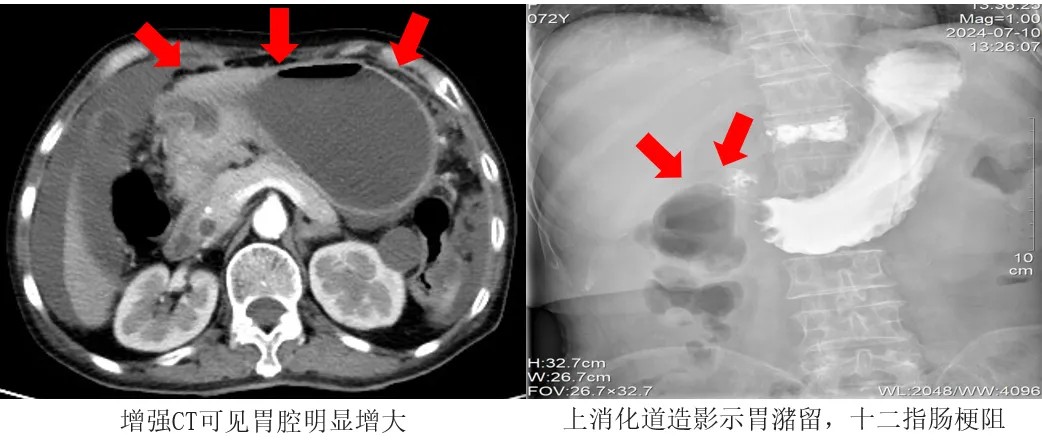

近日,江陰市人民醫院介入科成功為一名72歲胃癌晚期合并消化道梗阻患者置入十二指腸支架,不僅有效打通了患者的營養輸送通道,還顯著提升了其生活質量,為后續治療奠定了堅實的基礎。

不久前,72歲的王阿姨罹患胃癌,發現時已為癌癥晚期,癌細胞已擴散至腹腔,無法行外科手術根治。但腫大的腫瘤組織嚴重壓迫胃的幽門及十二指腸部分,導致消化道梗阻。

考慮到王阿姨高齡、手術耐受力差,介入科團隊決定為其行十二指腸支架植入術治療,用支架撐開腸道,讓狹窄部位恢復通暢。

術前,醫療團隊通過鼻腔將胃腸減壓管插入脹大的胃腔,通過負壓球吸引出了已積蓄多日的數千毫升的胃內液體,使胃的體積恢復正常。

術中,醫生拔除胃腸減壓管,隨后通過王阿姨口腔,利用導管與導絲配合,精準進行了幽門插管操作,并成功穿越了狹窄區域。緊接著,他們沿著導絲順利放置了一枚十二指腸支架,且在透視下確認了支架的位置完全符合要求。

術后24小時,王阿姨開始喝水。術后48小時,王阿姨開始進食米湯等流質食物。術后72小時,王阿姨進食蛋羹、爛面條等半流質食物。復查上消化道造影顯示,支架形態、位置均良好,術區未見明顯狹窄及滲漏。王阿姨恢復了正常飲食。